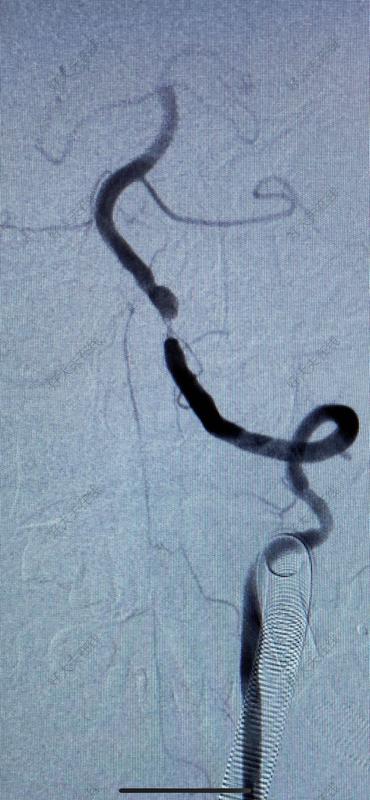

椎動脈閉塞3個月,介入開通

治療前患者男性,41歲,既往高血壓、高脂血癥病史,有吸煙及飲酒史?;颊?月前出現(xiàn)枕葉和小腦梗塞,1月前在當?shù)匦蠨SA發(fā)現(xiàn)左側椎動脈V1-V2(至C5水平)閉塞,枕動脈肌支自V3供血,并向近心端返流至C5水平,呈震蕩血流,考慮梗塞是由于震蕩血流造成椎動脈內斑塊脫落引起,患者存在罕見的椎動脈殘腔綜合征(VertebralArteryStumpSyndrome,VASS),這是后循環(huán)缺血性卒中的少見原因。治療中治療方案:因椎動脈起始端閉塞過長,故設計手術方案為頸外動脈-橈動脈-椎動脈搭橋(ECA-RA-VAbypass),術中行腦氧、TCD和電生理監(jiān)護等多模態(tài)監(jiān)護。該患者情況因為既往放置主動脈內覆膜支架無法行介入微創(chuàng)治療。治療后治療后1年術后腦灌注CT對比術前改善,術后患者訴視物光線較術前明亮清晰,術后一年復查搭橋血管通暢良好。